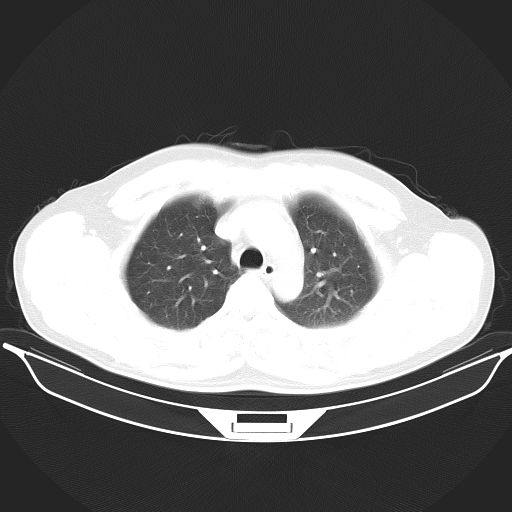

标题: CT25490:男,40岁,体检发现;无其它不适。 [打印本页]

标题: CT25490:男,40岁,体检发现;无其它不适。

考虑右下肺周围性肺癌并肺内多发转移,纵隔淋巴结转移!

支持 !考虑右下肺周围性肺癌并肺内多发转移,纵隔淋巴结转移,(气管前腔静脉后,隆突下,主动脉弓下都有了)